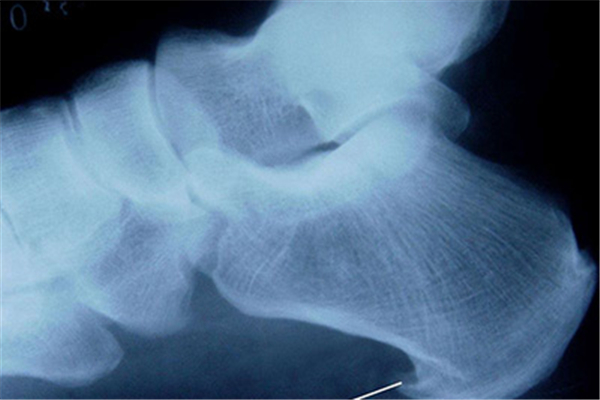

骨質(zhì)增生雖說(shuō)先開始的時(shí)候不會(huì)有什么癥狀,但是在后面的時(shí)候就會(huì)有疼痛的現(xiàn)象,這骨質(zhì)增生是因?yàn)槿笔裁礌I(yíng)養(yǎng)所引起的嗎?骨質(zhì)增生是缺鈣嗎?

骨質(zhì)增生并不是因?yàn)槿扁}所引起的,骨質(zhì)疏松卻和鈣有一定的關(guān)系。骨質(zhì)增生主要是由于周圍肌筋膜軟組織損傷而導(dǎo)致,由于基金膜損傷或者鈣化而導(dǎo)致局部牽引,長(zhǎng)時(shí)間對(duì)骨膜產(chǎn)生牽引而導(dǎo)致骨質(zhì)增生或者是骨刺。

骨質(zhì)增生是一種影像學(xué)的表現(xiàn)出,是骨關(guān)節(jié)退變致使,通常骨關(guān)節(jié)退變后局部穩(wěn)定性上升,反反復(fù)復(fù)的異常刺激致使局部自身的修補(bǔ)反映,再次出現(xiàn)骨質(zhì)增生,常再次發(fā)生于四肢的關(guān)節(jié)部位,和脊柱部位,病發(fā)早期可無(wú)明顯癥狀,當(dāng)炎癥明顯時(shí)有疼痛不適癥狀,口服非甾體抗炎藥救治,可以紓解疼痛,壓制纖維化的擴(kuò)張。需要強(qiáng)調(diào)的是注意多吃一些富含鈣質(zhì)和蛋白質(zhì)的食物,能夠促進(jìn)骨頭的生長(zhǎng)和愈合。

缺鈣和骨質(zhì)增生并沒有明顯的相關(guān)性骨質(zhì)增生的發(fā)生,主要就是由于運(yùn)動(dòng)量過(guò)度產(chǎn)生的,這種情況下就容易導(dǎo)致韌帶反復(fù)受到刺激,局部出血,最后形成了骨質(zhì)增生。隨著年齡的增長(zhǎng),身體鈣流失就會(huì)逐漸增加,這種情況就會(huì)導(dǎo)致缺鈣,需要積極的進(jìn)行補(bǔ)充鈣質(zhì)。